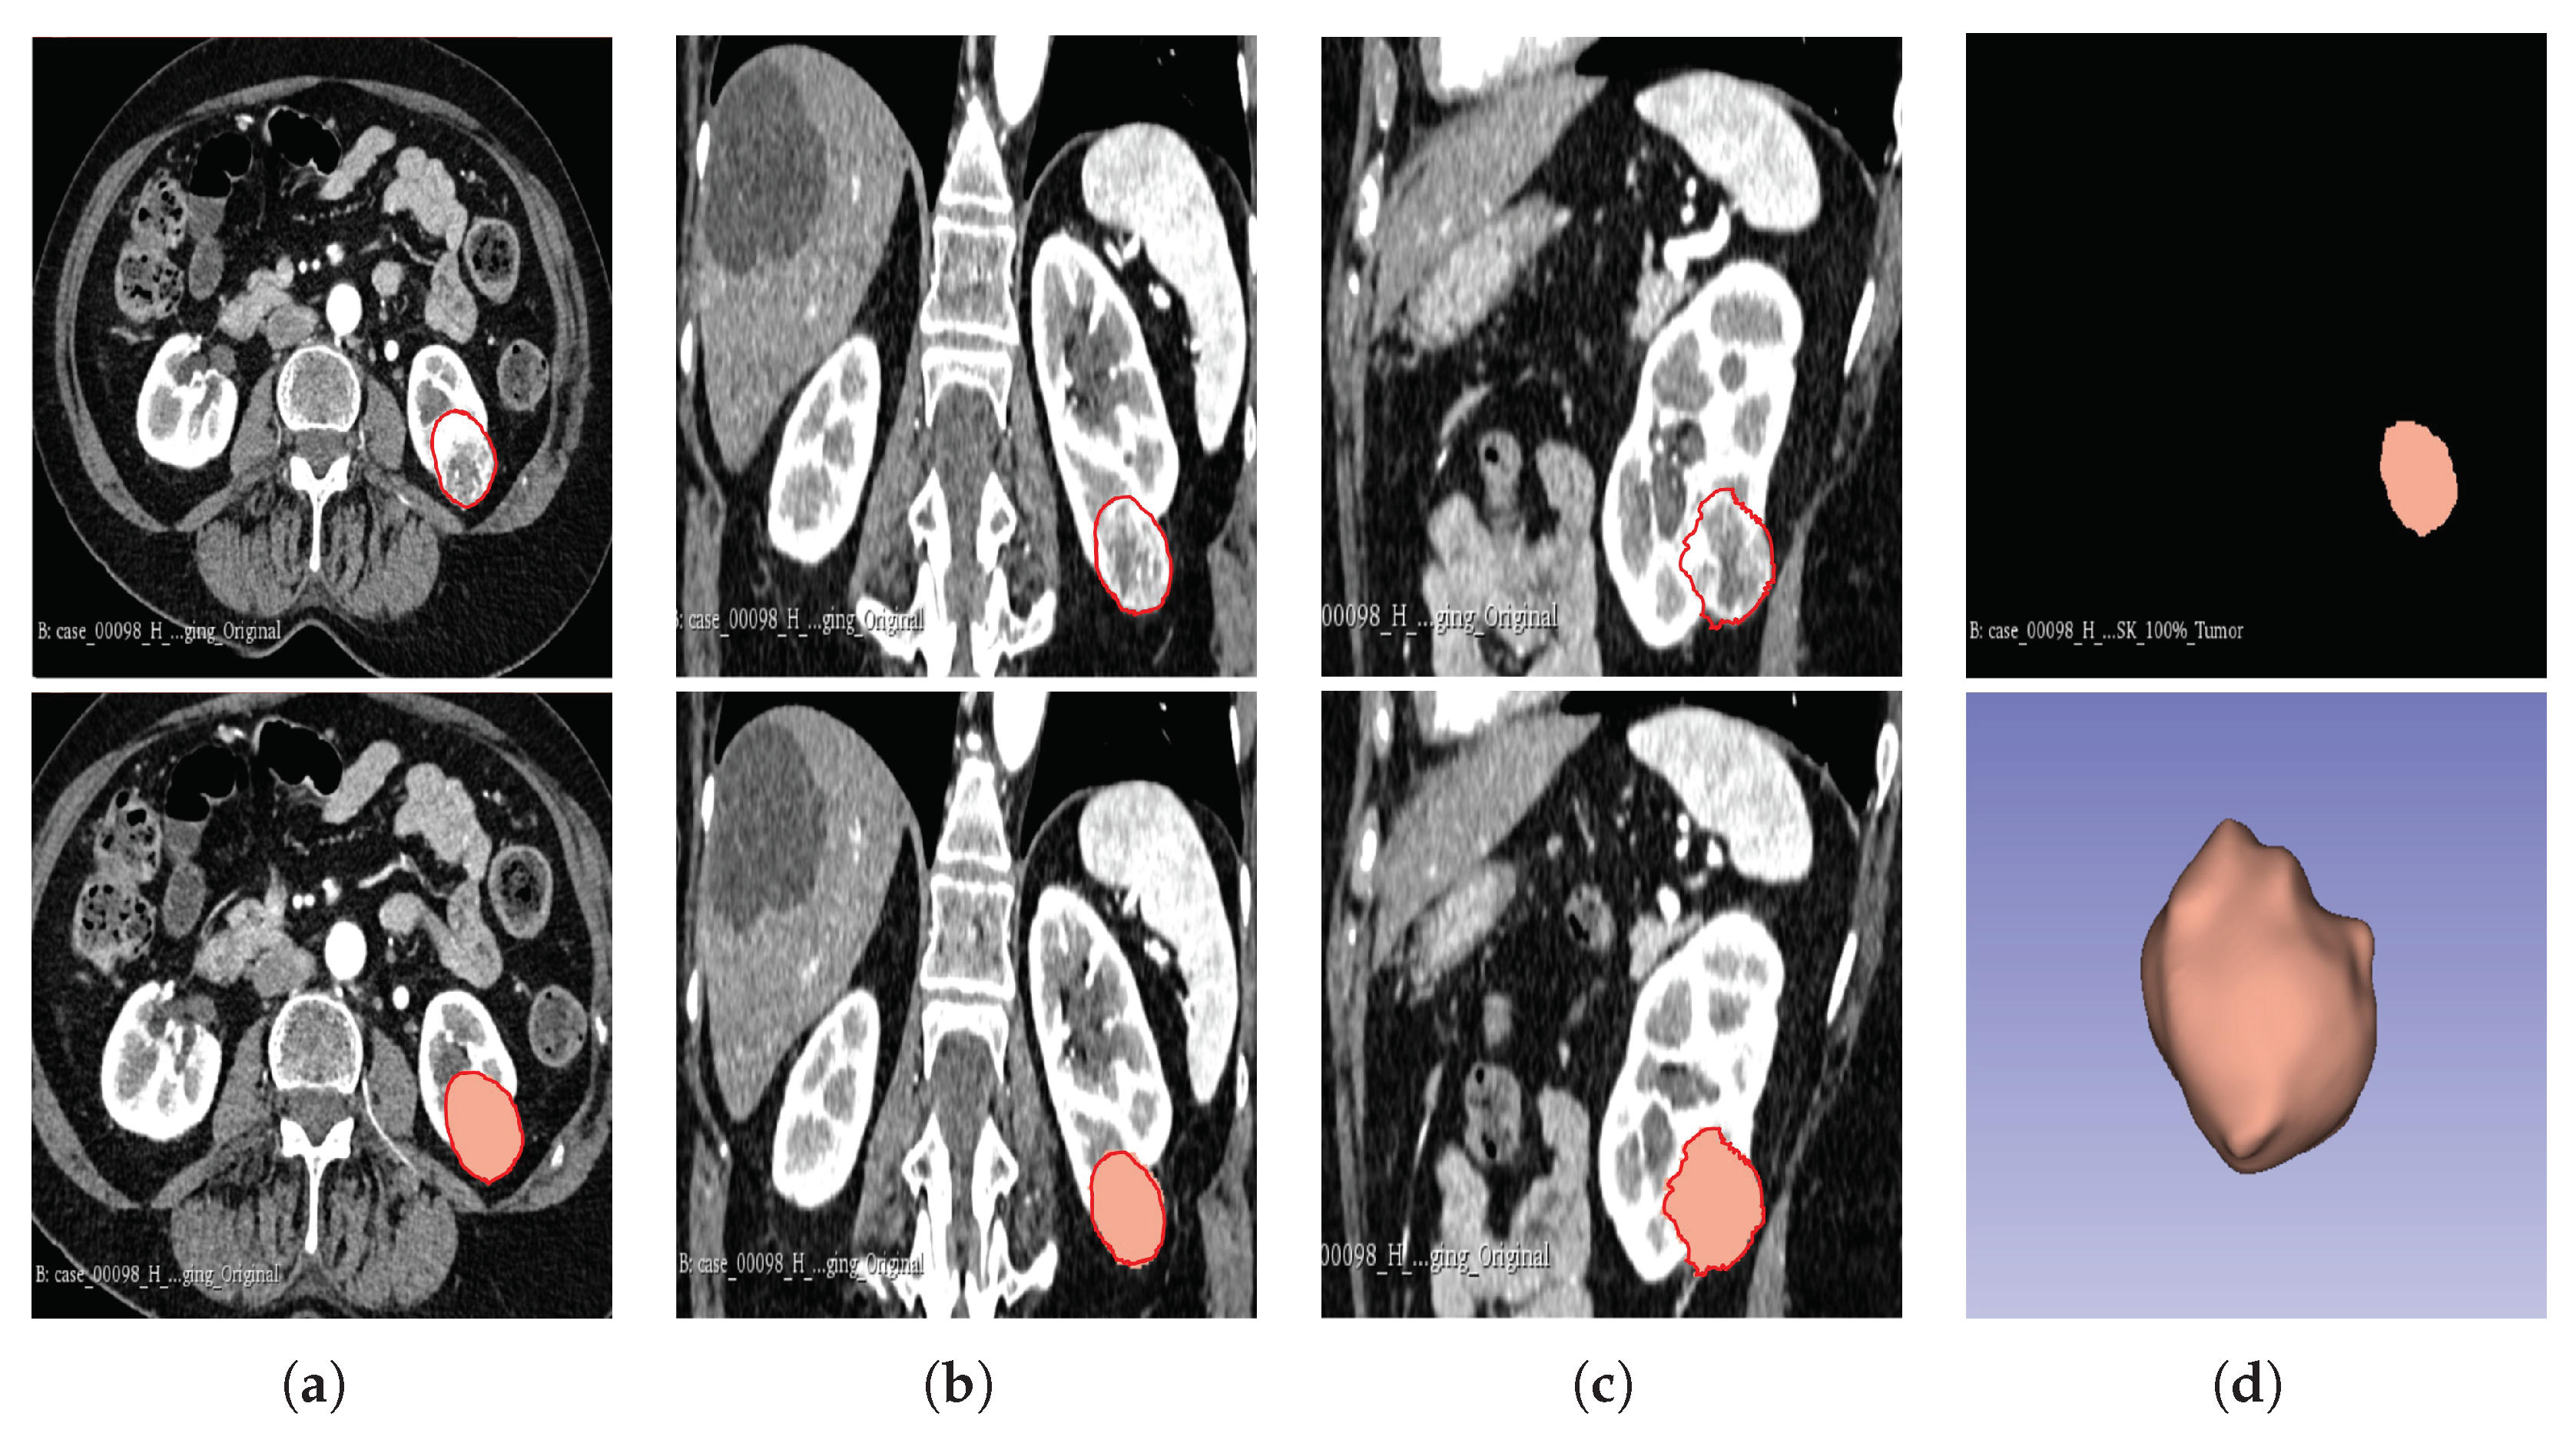

The segmentation result for both cohorts 1 and 2 was a binary mask of the tumour. In the present study, the tumours were divided into different sub-regions based on their geometry (i.e., periphery and core). The periphery refers to regions towards the edges of the tumour, whereas the core represents regions close to the centre of the tumour. The core was obtained by extracting 25%, 50%, and 75% of the binary mask from the centre of the tumour, while the periphery was generated `by extracting 25%, 50%, and 75% of the binary mask starting from the edges of the tumour to form a rim as a hollow sphere. A detailed visual description is shown in Figure 2, Figure 3, and Figure 4. Mask generation was performed using a Python script which automatically generated the sub-regions by image subtraction techniques.